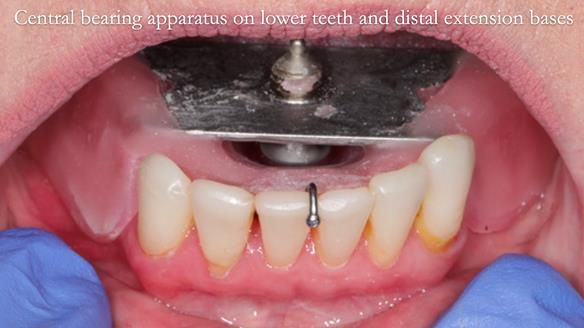

This newsletter describes the full protocol workflow of a complete upper denture and a lower partial denture for Jo.

The clinical situation and treatment process is shown in detail below. I provided the clinical work. Rowan Garstang provided the technical work. This treatment took 25 visits over a period of 12 months.